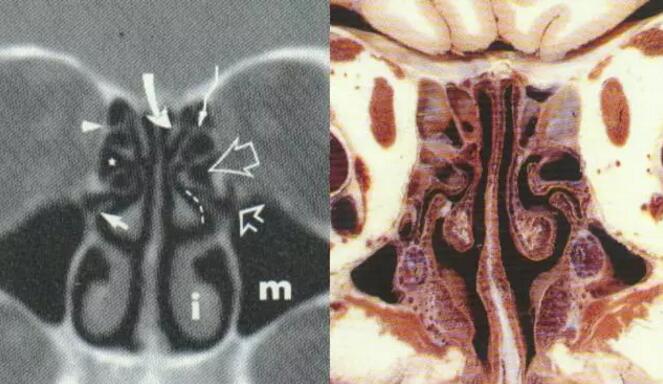

中鼻甲解剖变异:泡状中鼻甲

泡状中鼻甲感染及引起上颌窦口阻塞

中鼻甲解剖变异:筛甲气房

筛甲气房感染

中鼻甲解剖变异:中鼻甲反向弯曲

中鼻甲解剖变异与鼻窦炎